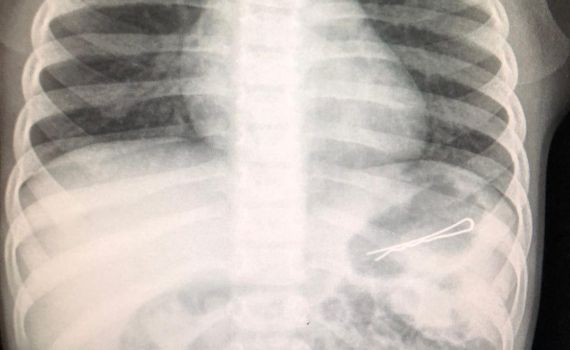

חייו של פעוט בן 3 ניצלו השבוע, לאחר שהובא למרכז הרפואי זיו כשבבטנו נמצאה סיכת ראש באורך 6 ס"מ אותה בלע.

בעקבות קושי בנשימה בוצע צילום רנטגן ובו נראתה בבירור הסיכה שהחלה לעבור בשער הקיבה ולכן היה צורך בביצוע גסטרוסקופיה, תוך החדרת צינור מהגרון לקשת התריסריון ושליפת הסיכה בזהירות רבה, כיוון שאחד מצדדיה חד.